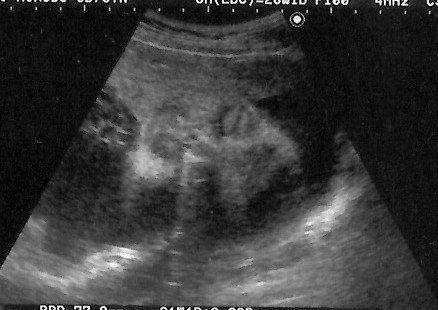

<妊娠初期ごろ>妊娠したうれしさより流産の不安におびえる日々

妊娠5週目のエコー写真 ようやく妊娠成立!

不妊治療専門クリニックで5回目の体外受精を行い、その後医師から妊娠していることを告げられました。妊娠5週目の画像です。当時は、妊娠したうれしさより、正直なところ「これでもうあの治療のつらさから解放されるかもしれない」という気持ちの方が強かったです。まだ流産の可能性が高いということで、夫も私も心から喜ぶことはできませんでした。